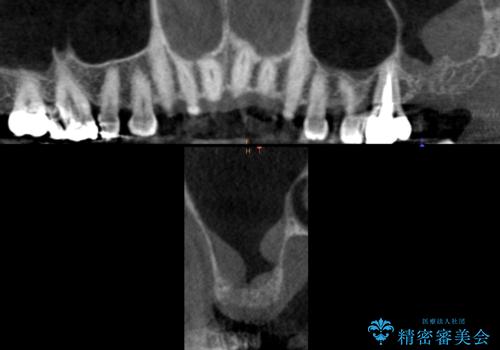

奥歯(左上7)のメタルインレー(銀の詰め物)を除去し精査したところ、奥歯はわれていました。

根尖近くまで深くヒビが入っており保存不可能な状態でした。

上顎洞が近接しており上顎骨の厚みが薄いことから、ソケットリフト(上顎洞底挙上術)をインプラント埋入と同時に行いました。